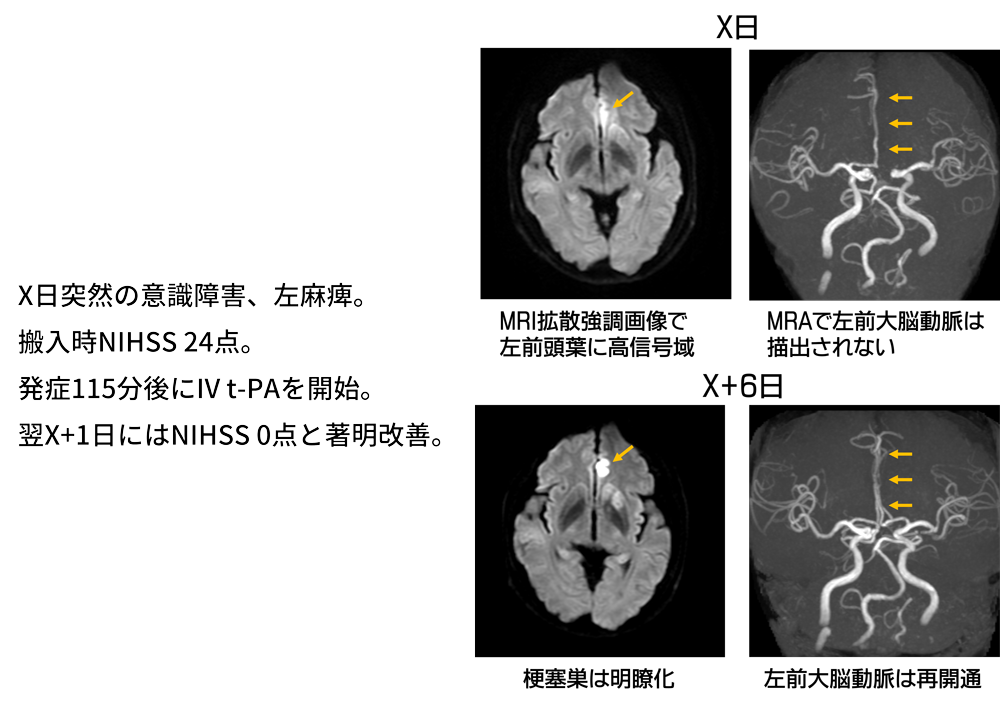

IV t-PAが著効した脳塞栓症の1例

治療の一例

| IV t-PA実施数 | 12例 |

|---|---|

| 血栓回収療法での転送数 | 7例 |

(令和4年度)